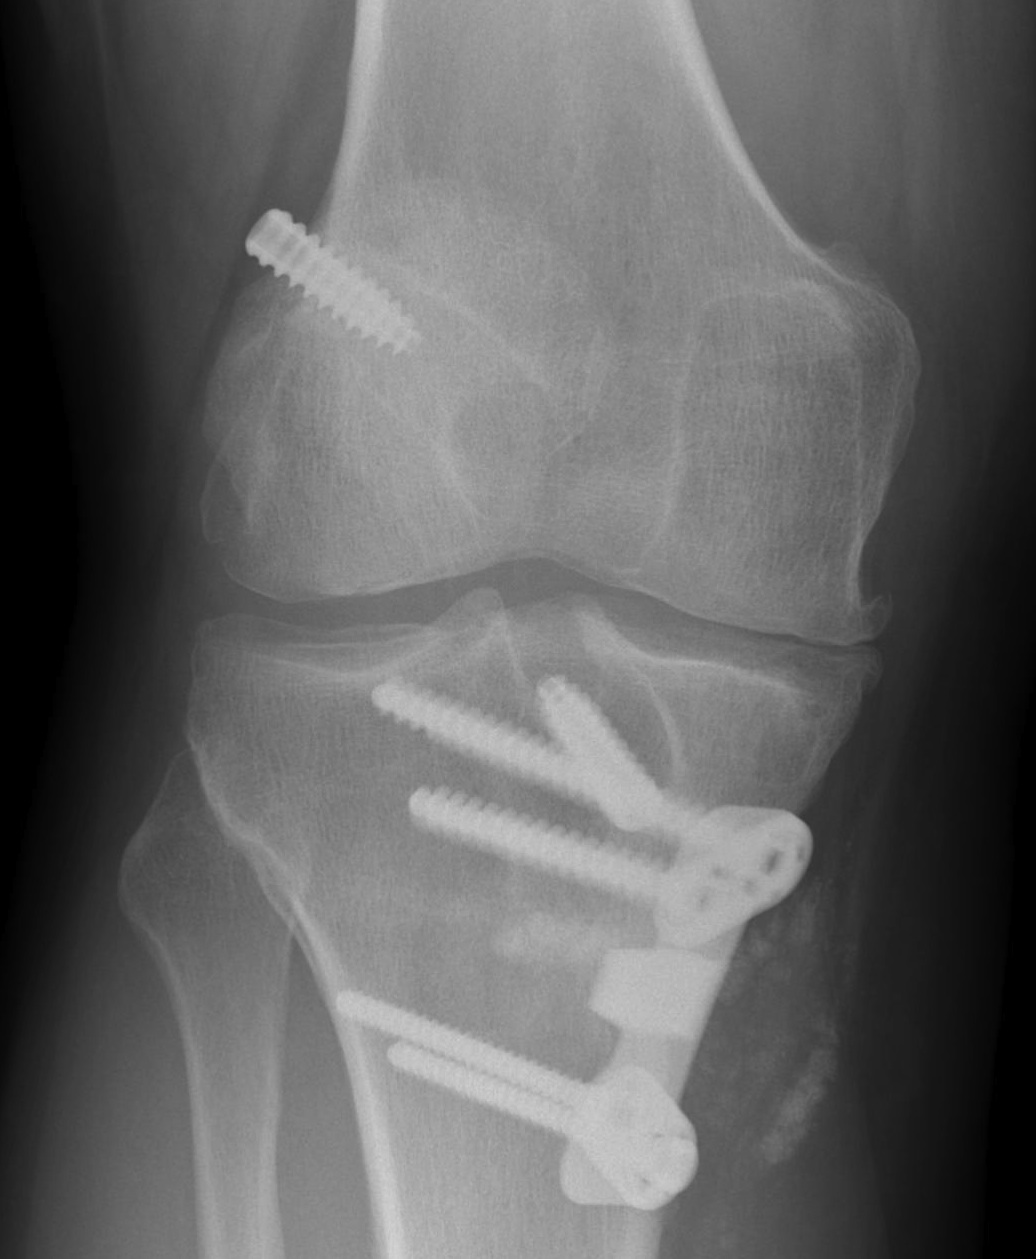

2. ACL + Medial Collateral

Epidemiology

Grade II MCL

- 75% chance ACL rupture

Non-operative

Rehab MCL

- perform delayed reconstruction of ACL if symptomatic instability

ROM knee brace to limit extension

- 2 weeks 30-60°

- 2-4 weeks 30-90°

- 4-5 weeks 15˚ - 90

- 6th week 0 – 90˚

Indication for surgery

- MCL torn off tibia (usually off femur) and flipped up and over the pes anserinus

- won't heal in this position

- MRI all patients with MCL tenderness over tibal insertion

Patient with MCL and ACL instability

- reconstruct ACL

- reassess MCL at end of case

- if mildly unstable, advance / imbricate MCL on femoral side +/- tighten medial head gastrocnemius

- if severely unstable, reconstruct with hamstring or tendoachilles allograft